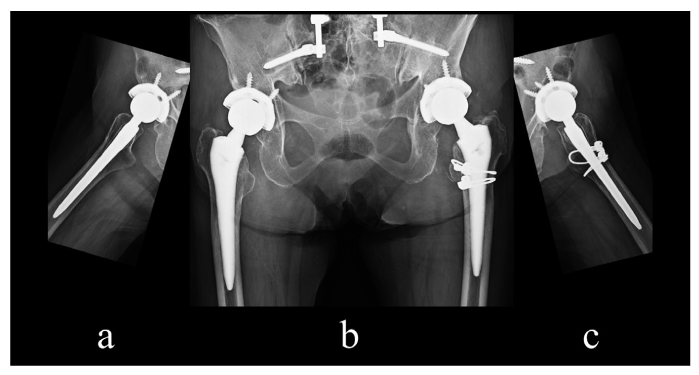

Fig. 10

Fig. 10 Follow-up X-ray image of bilateral revision total hip arthroplasty after 5 years. Notice the radiolucent line in zones 1, 8, 14 in both hips without sinking of the stem, osteolysis, or implant loosening. (a) Anteroposterior view, (b) right lateral view, (c) left lateral view.